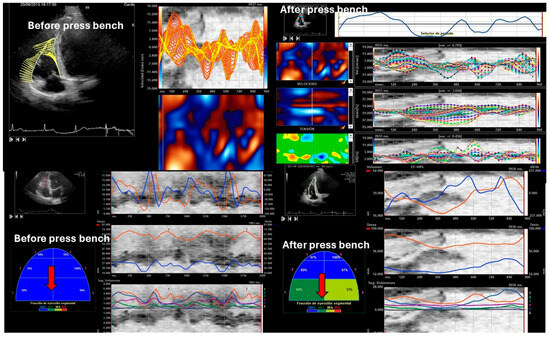

3.4. Right Ventricular Systolic Function

| 3D RVEF (%) | 0.67 ± 0.06 | 0.55 ± 0.22 | 0.78 ± 0.12 | 0.001 |

| IVA (m/s2) | 2.38 ± 0.22 | 3.52 ± 0.15 | 6.66 ± 0.88 | 0.001 |

| S’ wave (cm/s) | 12.27 ± 1.13 | 14.52 ± 0.09 | 18.38 ± 1.21 | 0.001 |

| TAPSE (mm) | 24.33 ± 3.12 | 19.08 ± 5.14 | 27.45 ± 3.21 | 0.001 |

| Global RVEF 2D | 0.62 ± 0.15 | 0.49 ± 0.06 | 0.74 ± 3.21 | 0.001 |

| Laterobasal RVEF | 0.65 ± 0.25 | 0.42 ± 0.02 | 0.94 ± 0.17 | 0.001 |

| Lateromedial RVEF | 0.62 ± 0.12 | 0.55 ± 0.18 | 0.74 ± 0.22 | 0.001 |

| Lateroapical RVEF | 0.62 ± 0.09 | 0.49 ± 0.17 | 0.95 ± 0.19 | 0.001 |

| Septoapical RVEF | 0.63 ± 0.15 | 0.47 ± 0.18 | 0.95 ± 0.21 | 0.001 |

| Septomedial RVEF | 0.65 ± 0.21 | 0.46± 0.22 | 0.98 ± 0.17 | 0.001 |

| Septobasal RVEF | 0.58 ± 0.22 | 0.43 ± 0.02 | 0.94 ± 0.19 | 0.001 |

| Peak systolic longitudinal velocity (cm/s) | 4.98 ± 0.12 | 4.01 ± 10.21 | 9.48 ± 3.25 | 0.001 |

| Right ventricular longitudinal global strain (%) | −27.31 ± 1.47 | −23.55 ± 2.37 | −30.98 ± 2.12 | 0.0001 |

| Right ventricular Longitudinal Strain delay (ms) | 144.88 ± 22.52 | 168.92± 29.35 | 98.27 ± 12.11 | 0.0001 |

| Right ventricular longitudinal global right Strain rate (1/s) | −1.79 ± 0.078 | −1.48 ± 0.33 | −2.88 ± 0.25 | 0.0001 |

| Right ventricular Longitudinal systolic displacement (mm) | 6.12 ± 1.18 | 5.09 ± 3.22 | 10.88 ± 1.25 | 0.0001 |

| Right ventricular Radial systolic displacement (mm) | 1.88 ± 1.78 | 1.33 ± 1.14 | 4.57 ± 0.96 | 0.0001 |

| Right ventricular Radial displacement delay (ms) | 182.14 ± 17.12 | 212.36 ± 18.96 | 124.32 ± 15.25 | 0.0001 |